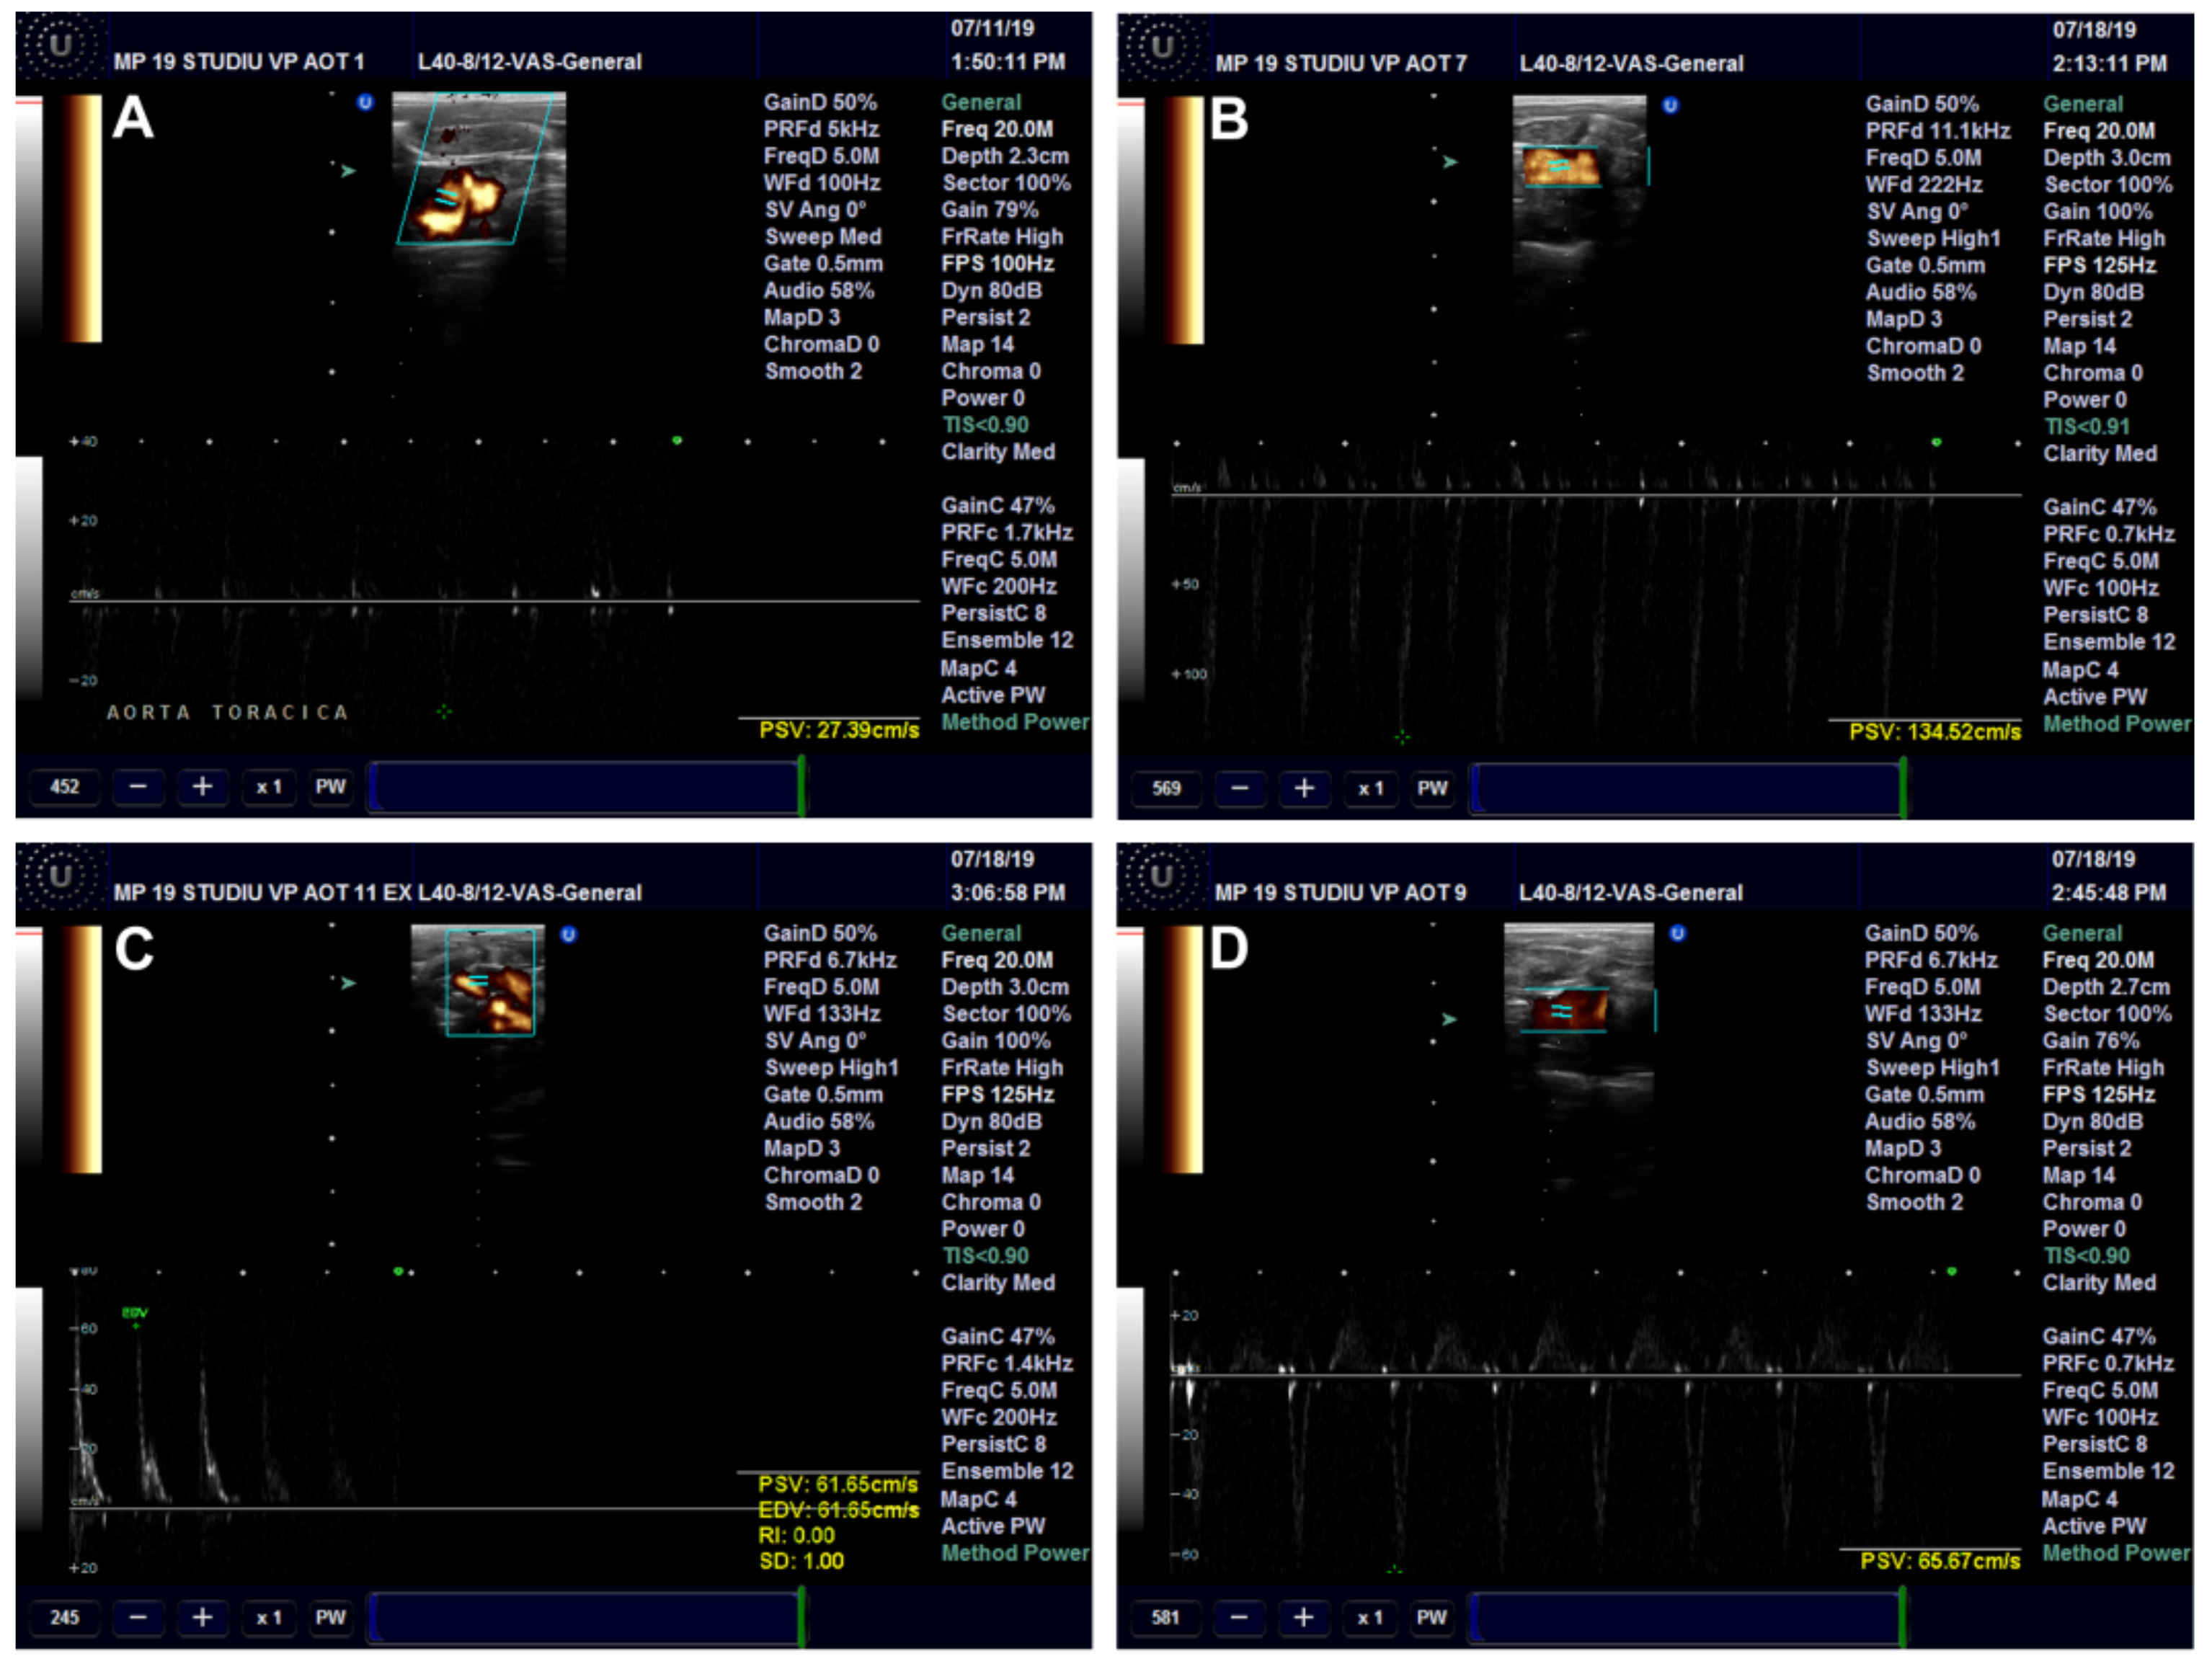

Ultrasound Examination of the Aorta and Left Ventricle